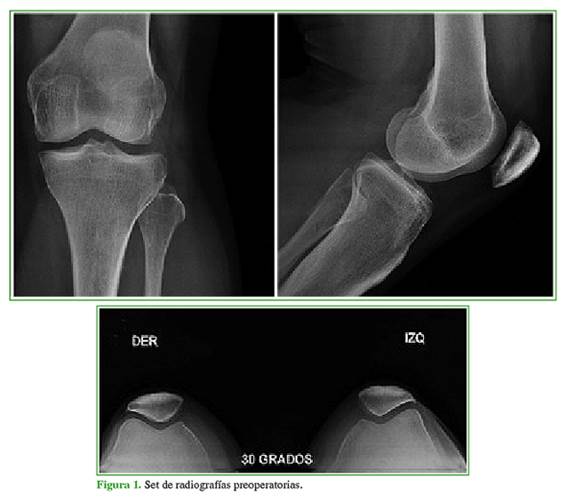

Mujer de 32 años con dolor crónico de origen rotulofemoral en la rodilla izquierda y limitación para caminar en superficies inclinadas. Las radiografías anteroposterior y lateral de rodilla, y tangencial de rótula mostraban cambios artrósicos de la rótula (Figura 1). En enero de 2018, una resonancia magnética de rodilla reveló una lesión condral de la rótula grado IV. Se indicó rehabilitación e infiltración con corticoides, pero el dolor no mejoró (Figura 2). El 13 de febrero de 2018, fue sometida a una cirugía con aloinjerto fresco de rótula (Figura 3). La evolución fue satisfactoria, sin dolor ni derrame articular, los arcos de movilidad eran de 0° a 100°, no tenía limitaciones para caminar. En la radiografía y la tomografía computarizada de rótula (septiembre de 2018), se observó la incorporación del injerto (Figura 4).